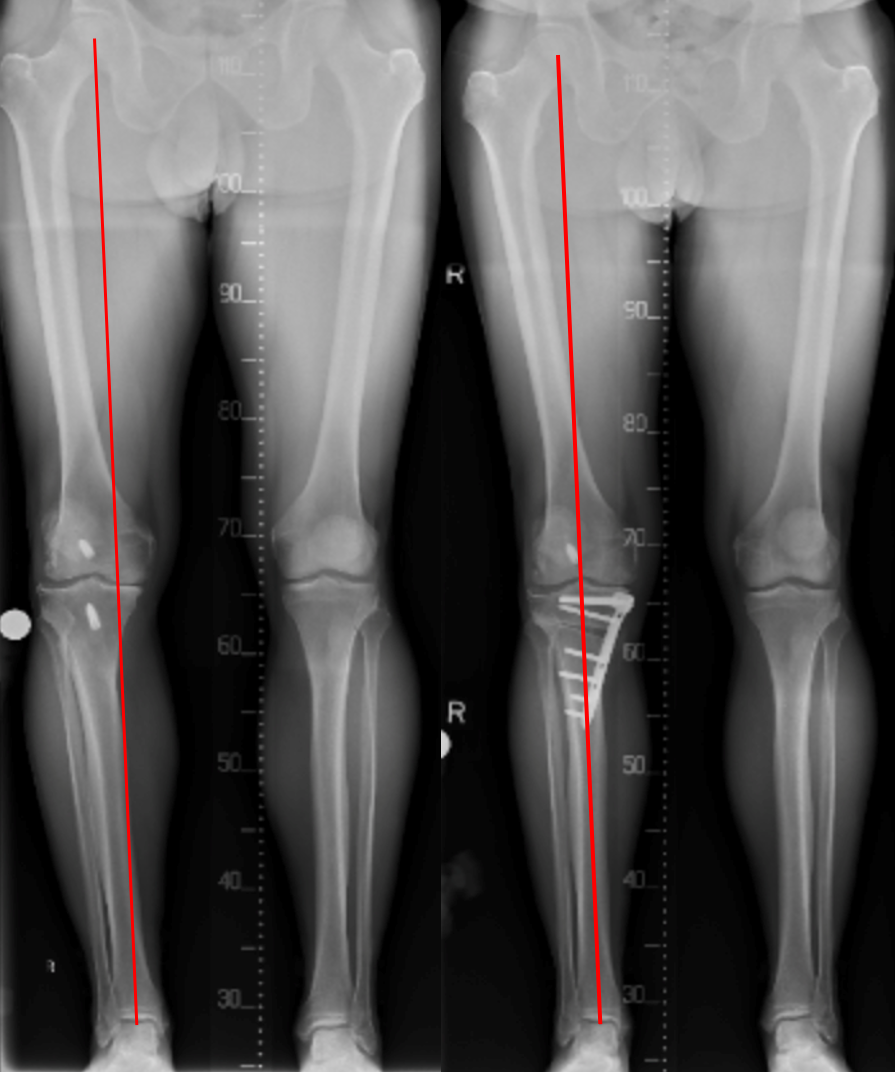

Pre-op and Post-op Osteotomy showing change in the weight-bearing line away from the damaged part of the knee.

When standing, the weight of the body usually falls in a straight line from the centre of the hip to the centre of the ankle, passing through the centre of the knee. Due to trauma or arthritis the knee may become progressively more bowed (varus) or knock-kneed (valgus). Occasionally bowed or knock-knee deformity develops in adolescence without an apparent cause.

In a bowed knee the bodyweight falls through the inner side of the knee. In an arthritic knee this creates a vicious cycle in which there is more wear on the inside of the knee, which increases the deformity and so on. The wear is more advanced on the outside of a valgus knee.

We carefully calculate the angle of correction, and the size of the triangle to be opened or closed, in advance of the surgery. Our calculations are bases on an xray of your whole leg, and computer software which simulates the correction and works out the most desirable correction to the nearest millimetre.